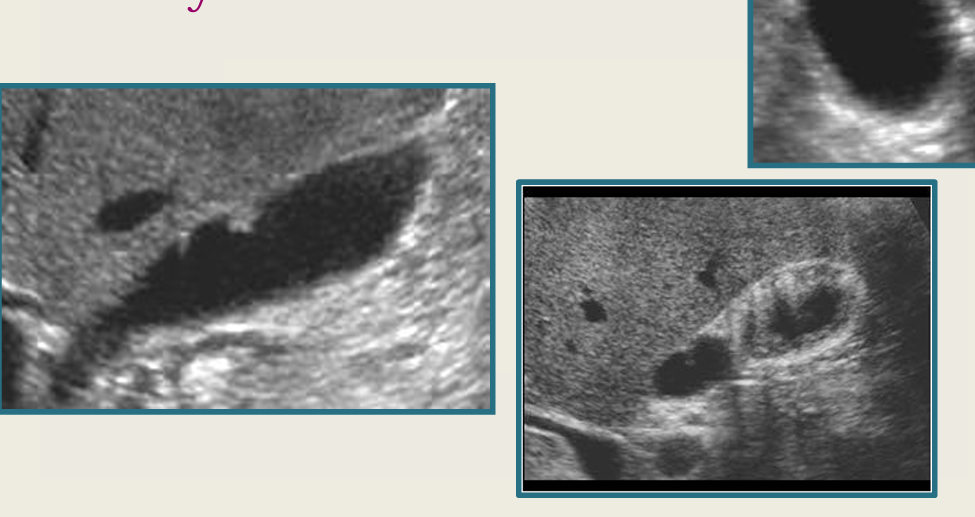

term image

adenomyomatosis

strawberry GB

mucocele